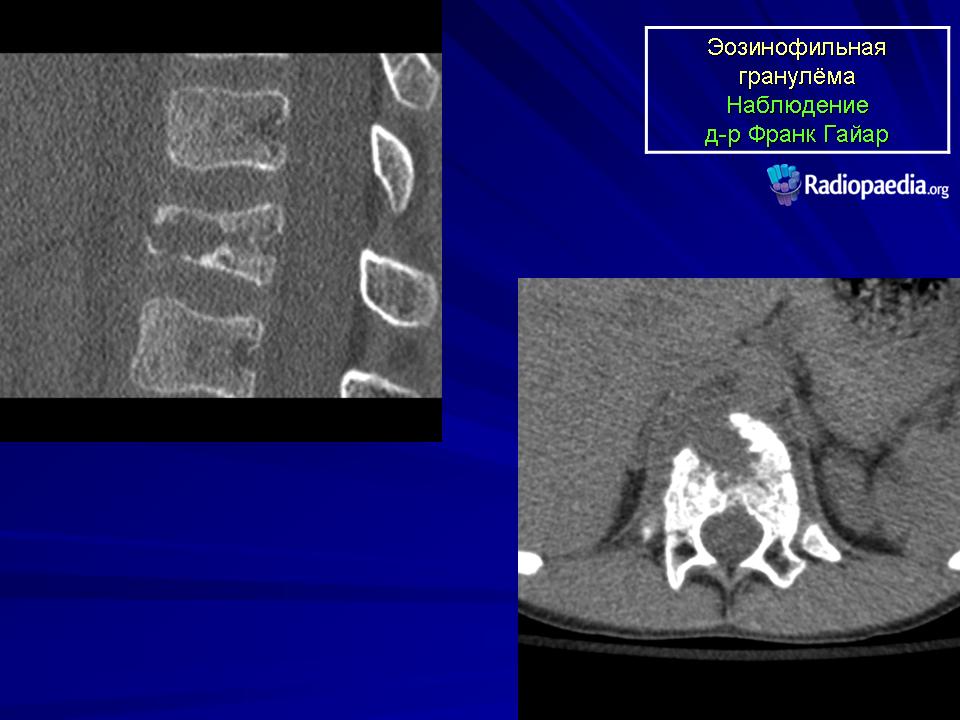

Продолжение.